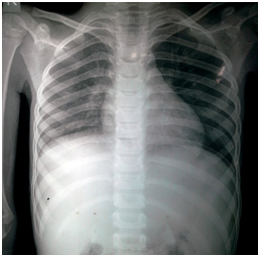

A 10-year-old male, hailing from Ratnagiri district of Maharashtra, India was admitted to the hospital, with history of fever accompanied by fronto-parietal headache and body ache for 1 month. He also complained of productive cough with expectoration and breathlessness for 15 days. The patient was diagnosed with Human Immunodeficiency Virus (HIV) infection 1 month before admission, following which he was started on anti-retroviral therapy (ART). His mother was diagnosed with HIV infection 3 years ago and was started on ART. His father was also diagnosed with the same 2 months back, but was not on treatment. The patient had a 13 year old sibling who was HIV seronegative. Local examination revealed gross emaciation, small subcutaneous nodules about 3-5 mm in diameter over face (Figure 1) and palpable post auricular & bilateral medial axillary lymph nodes. Neurological examination did not reveal any meningeal signs apart from brisk plantar reflexes. Haematological parameters showed macrocytic anaemia with anisocytosis on peripheral blood smear, gross leucopenia (1900 cells/mm3) and mildly elevated Erythrocyte Sedimentation Rate (ESR 35mm at 1 hour). Serum creatinine was high (1.2 mg/dl). He had hypokalemia and severe Vitamin B12 deficiency. CD4 count was markedly reduced (8 cells/mm3). Chest X-Ray revealed diffuse infiltration in the right middle and lower lobes (Figure 2). Ultrasonography (USG) of abdomen revealed multiple, non-necrotic retroperitoneal lymphadenopathy. Computed tomography (CT) scan of brain showed age unrelated atrophy (Figure 3).

Figure 2 Chest X-Ray showing diffuse infiltration in right middle and lower lobes.

In our case, meningeal symptoms had preceded respiratory symptoms, though the natural history of the disease suggests a primary respiratory route followed by dissemination. Radiological presentations in pulmonary cryptococcosis are varied and nonspecific including nodules, consolidation, cavitary lesions, and a diffuse interstitial pattern, influenced by the underlying immune status of the patient. In our case, diffuse infiltration was noted in the right middle and lower lobes on chest X-Ray. Diagnosis is based on isolation of Cryptococcus from, or detection of cryptococcal antigen in a pulmonary specimen, coupled with appropriate clinical, radiological, and histopathological findings. Among eight paediatric cryptococcosis cases reported between 2005 and 2015 (4 cases from India and 4 from other countries).5,10-13 Cryptococcus sp. was never isolated from sputum. Cryptococcus neoformans is rarely seen in sputum and culture may occasionally be positive. In adults, pulmonary cryptococcosis has been reported mostly in immunocompromised patients. Even among these, documentation of Cryptococcus sp. in sputum is lacking. Most of these cases have been diagnosed on histopathology or only in culture. Direct microscopy for sputum was positive in only 2 cases but there is no photographic documentation in these reports.14,15 Treatment recommendations include induction therapy with an amphotericin B preparation and flucytosine for immunocompromised patients and those with severe disease and fluconazole for mild-to-moderate, localized disease.16 In our case, induction therapy was initiated with IV amphotericin B and flucytosine, followed by fluconazole as consolidation and maintenance therapy.